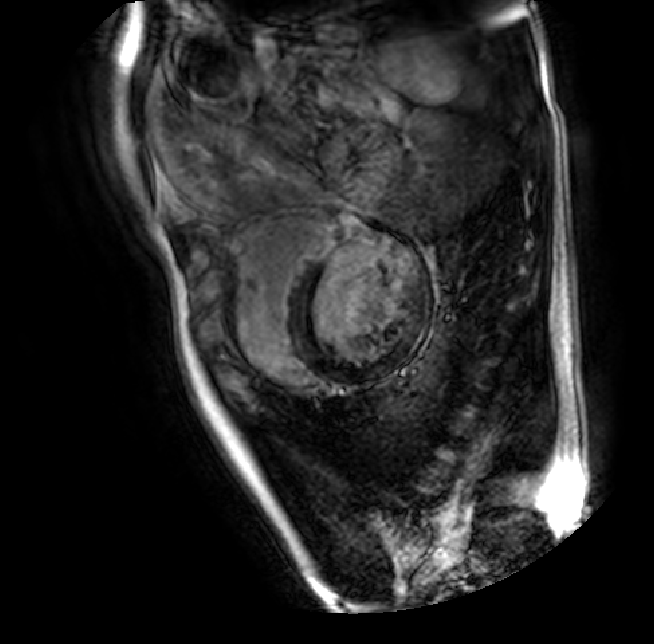

Table 2 presents an ablation study and compares SparseMamba-PCL with nine SOTA scribble-supervised methods across the three datasets. Out method achieves the highest Dice score across all the datasets, and the lowest (CHAOS) and second lowest (ACDC and MSCMRSeg) HD95 values, confirming its effectiveness in segmentation accuracy and boundary refinement. Baseline+SPOBE and Baseline+PCL improve upon the Baseline (SparseMamba), demonstrating the benefits of boundary-aware supervision and SAM-guided learning. Fig. 4 (l) compares the segmentation performance of SparseMamba-PCL with other scribble-supervised methods, showing smoother edges that precisely delineate object boundaries, unlike the jagged or blurred edges in other methods. The examples also demonstrate the consistent segmentation quality achieved by SparseMamba-PCL across ACDC, CHAOS, and MSCMRSeg, highlighting its adaptability across multiple medical domains. This adaptability and precise segmentation is crucial for accurate volumetric analysis and clinical decision-making, where even subtle boundary inaccuracies can lead to diagnostic errors. In summary, the SparseMamba-PCL architecture provides a consistent and robust improvement in segmentation metrics across diverse medical image datasets.

Refer to caption Refer to caption Refer to caption Refer to caption Refer to caption Refer to caption Refer to caption Refer to caption Refer to caption Refer to caption Refer to caption Refer to caption

(a) (b) (c) (d) (e) (f) (g) (h) (i) (j) (k) (l)

Figure 4: Qualitative comparison of weakly-supervised segmentation methods on ACDC, CHAOS, and MSCMRSeg datasets. (a) Input image, (b) ground truth, and segmentation results from (c) USTM [16], (d) Scribble2D5 [5], (e) CycleMix [26], (f) ShapePU [27], (g) S²ME [21], (h) ScribbleVC [12], (i) TDNet [30], (j) PacingPseudo [25], (k) Scribbleformer [13], and (l) SparseMamba-PCL are given.